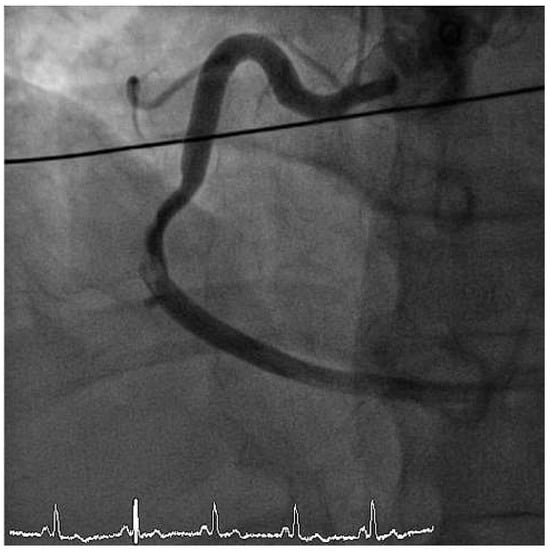

Furthermore, the right coronary artery showed a subtotal thromNo botic occlusion (Figure 3). Prior to the local treatment, a bolus of heparine 5000 IU and Abciximab were administered due to the heavy thrombus load. Thrombus aspiration was performed using an aspiration-catheter (Export AP, Medtronic) in all three coronary vessels. Due to persistent thrombotic material in the mid LAD, two low-pressure balloon inflations were done with a good end result (Figure 4 and Figure 5). There were no periprocedural complications. A treatment with life-long aspirin, one-year prasugrel, Betablocker and ACE-Inhibitor was initiated. The next day, a transesophageal echocardiography demonstrated improved LV-function (EF 50%) without evidence for an intracardiac thrombus or a patent foramen ovale (PFO).

Figure 4. RAO view showing good end result after thrombus aspiration in LAD and RCX and PTCA of the LAD.